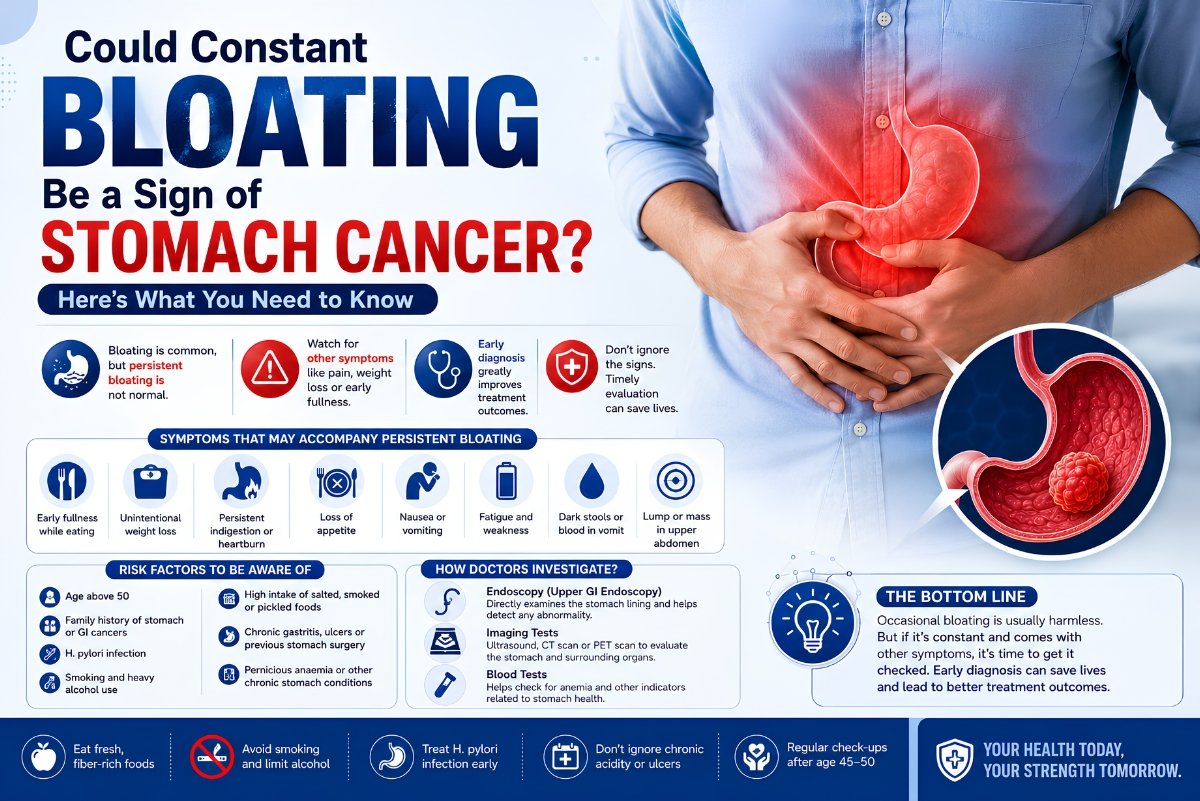

Could Constant Bloating Be a Sign of Stomach Cancer?